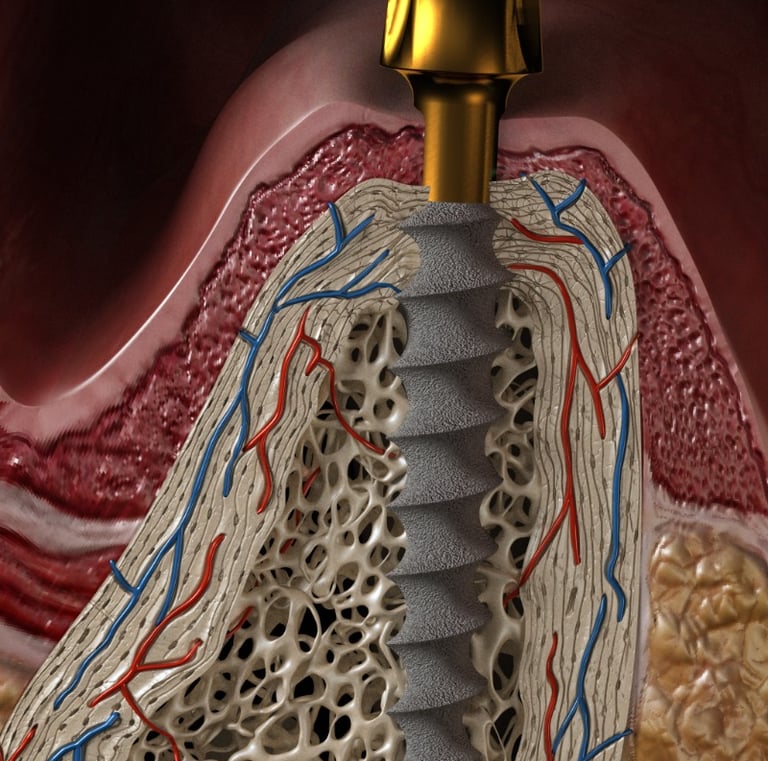

Implantes Monobloque

Implantes dentales sin cirugía.

Sin abrir encía.

Sin puntos de sutura.

Ideal para personas con poco hueso o edad avanzada.

Dientes inmediatos / 24 horas .

Implantes dentales innovadores

Implantes

Implantes monobloque sin cirugía y dientes inmediatos.